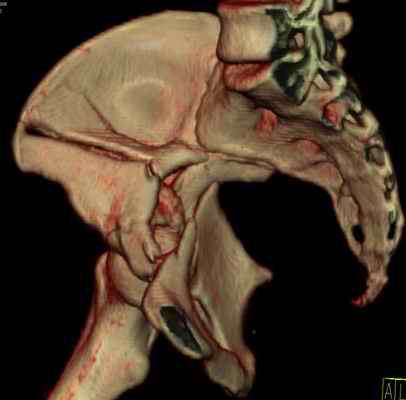

Посылаю схемы и 3D реконструкцию подобного повреждения. Называется он полным высоким двухколонным переломом вертлужной впадины, а "переломы крыла и тела подвздошной кости" входят в это понятие.

прикладываю схему доступа и случай.